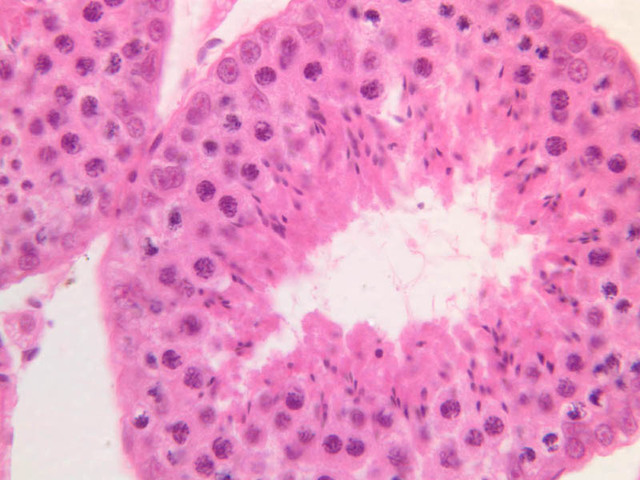

Sperm production, or spermatogenesis, encompasses two distinct series of events: one affecting mostly the nucleus, the other affecting mostly the cytoplasm. First, there is a series of events, known collectively as spermatocytogenesis, in which rounded diploid stem cells (spermatagonia) give rise to clusters of rounded haploid cells (spermatids). Then there is a series of events, known collectively as spermiogenesis, in which the round spermatid spins a long flagellum, undergoes compaction of its nucleus, transforms its Golgi complex into an acrosomal cap, and sheds nearly all of its cytoplasm to yield a spermatazoa. Bear in mind that if you are to develop a good sense of the dynamics of sperm production, you will have to examine a number of seminiferous tubules. This is because spermatogenesis is typified by complex waves of proliferation and differentiation that sweep both around the circumference and along the length of the seminiferous tubule. Using the high dry objective, search slide B-81 for a transversely sectioned seminiferous tubule (i.e. one that presents a round profile in which a large lumen is surrounded by an epithelial wall of uniform thickness). Observe that the peripheral surface is demarcated by a continuous layer of small flattened cells containing elongated basophilic nuclei. These are contractile myoid cells (similar to the myoepithelial cells of other glands), which aid in propulsion of the luminal contents towards the excurrent duct system (B-81, testis, PAS [2.5x-labeled, 10x, 20x. 40x-labeled]; [10x, 20x, 40x]). The clearly stratified seminiferous epithelium differs in appearance from one tubular profile to another and even from one part of a single tubule to another. The seminiferous epithelium is composed of two populations of cells: proliferating cells of the germinal spermatogenic series and nonproliferating Sertoli cells. Sperm production begins with mitotic division of cells located at the tubule periphery; later events occur progressively closer to the lumen. In typical H&E preparations of seminiferous epithelium it is the distinctive qualities of nuclei that stand out against poorly defined cytoplasm (B-80, testis, H&E [20x, 40x-labeled] [10x, 20x, 40x-labeled] [10x, 20x, 40x] [2.5x, 10x, 20x, 40x]; B-82, testis, H&E [2.5x, 10x, 20x, 40x] [2.5x, 10x, 20x, 40x] [10x, 20x, 40x] [10x, 20x, 40x]). Thus, in your study of seminiferous epithelium, it is nuclear appearance that will enable you to distinguish the following cell types:

Primary Spermatocytes

Primary spermatocytes originate from mitotic division of spermatogonia and are usually one or more cell diameters removed from the tubular periphery. Their nuclei are more or less spherical and are conspicuously larger than those of other germ cells; their chromatin is usually condensed into many thread-like structures. Most primary spermatocytes are seen in some stage of the very protracted (21-day) prophase leading up to the first meiotic (reduction) division, in which each primary spermatocyte gives rise to two secondary spermatocytes.

Spermatids

Spermatids are located next to lumen of the seminiferous tubule, where they undergo an elaborate differentiation process (spermiogenesis) that requires about 7 weeks and involves condensation of nuclear chromatin, compaction and elongation of the nucleus, shedding of nearly all cytoplasm and formation of a motile flagellum (tail). Spermatid nuclei vary in size, condensation of chromatin and shape according to the stage of spermiogenesis that they represent; however, all of them are smaller than the nuclei of any of the antecedent cell types. Spermatids at different stages of spermiogenesis may be present in a single tubule.

Sertoli cells

Interspersed among the germ cells, but generally situated near the epithelial periphery, are nuclei of the Sertoli cells. Sertoli cells span the full thickness of the seminiferous epithelium; however, because of their irregular shape and poor affinity for dyes, it is impossible to define the cytoplasmic processes of Sertoli cells in ordinary paraffin sections. Sertoli cells have large euchromatic nuclei and very prominent nucleoli. The nuclear shape is usually oval or triangular, but may also be irregular due to deep indentations of the nuclear membrane. The long axis of the nucleus is typically oriented at right angles to the basement membrane. From ultrastructural studies it is known that Sertoli cell processes make specialized contacts with germ cells as well as with processes of other Sertoli cells. Sertoli cells are the basis of the blood-testis barrier As you might expect, there are marked differences between the prepubertal and postpubertal testis. In the true prepubertal male (slide B-86, epididymis and testis, H&E [2.5x, 10x, 20x, 40x]) and in undescended testes of older males, the seminiferous tubules are solid cords of cells, consisting of spermatogonia-like cells known as gonocytes, and cells that resemble the Sertoli cells of the adult testis. Section B-78 is from the testis of an older individual and a lumen is now present (B-78, H&E [2.5x, 10x, 20x, 40x]). Even though the seminiferous epithelium of this autopsy specimen is poorly preserved, you should be able to evaluate its spermatogenic capacity. Can you identify spermatogonia and Sertoli cells? Are spermatids present? Judging from the interstitial morphology, would you expect high peripheral testosterone levels?